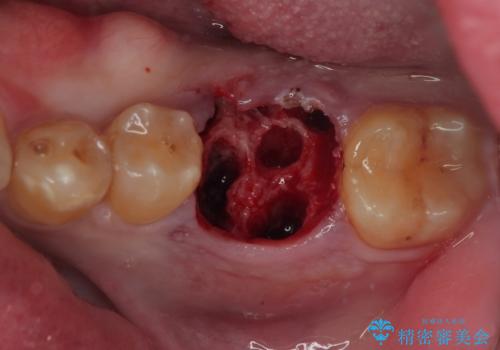

歯槽骨の状態は良好であったため、抜歯即時埋入インプラントによる補綴治療を行うこととしました。

インプラント埋入時に植立具合の安定性を測定したところ、十分な数値が得られたため、速やかに仮歯を装着して咬合回復をさせることができました。

抜歯を含めた外科処置を1回に抑えることができ、あっという間に治療を終えることができました。